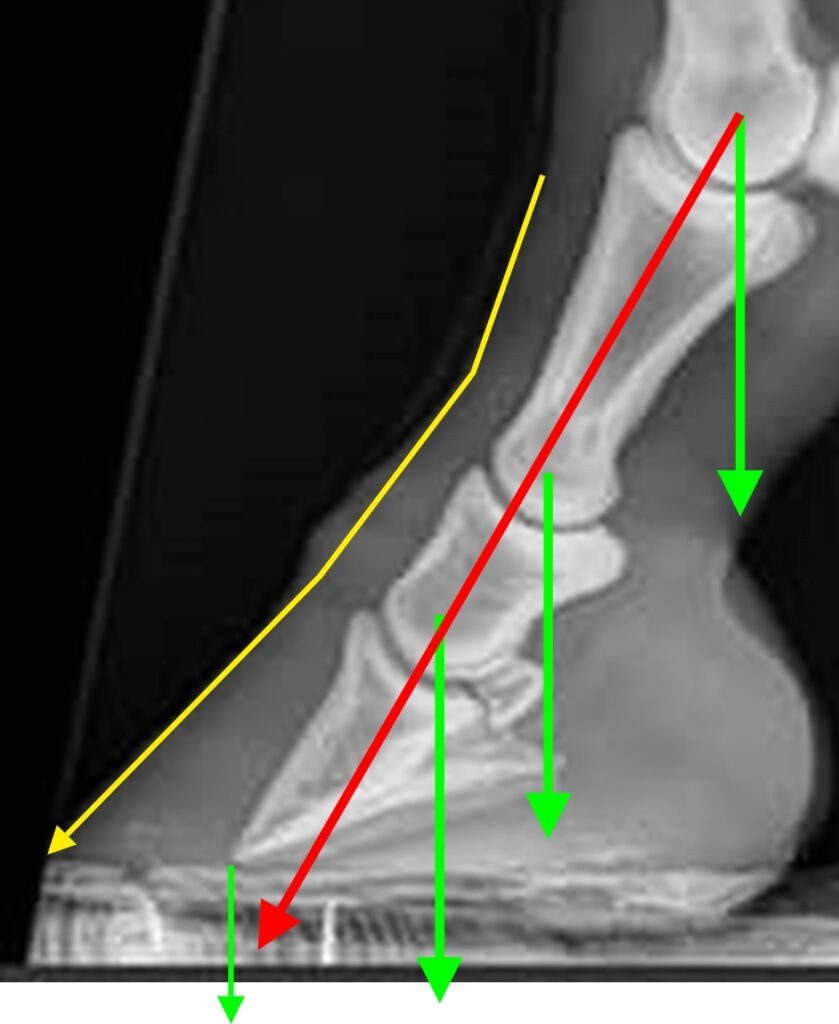

Toe axis, broken or not, is a purely theoretical concept. They say that the lowest three phalanges (P1, P2, P3) in the horse’s leg are supposed to be aligned (as the red line in the picture below) or the horse is suffering from a broken toe axis. There are multiple problems with this reasoning. As you can see in the picture above, there is no standard or fixed angle on the lower three phalanges when the horse is moving. It is alldepending on the loading of the hoof. Yes, I’ve heard that you are supposed to check the toe axis when the horse is standing still, in balance, on a flat surface. But why, when standing still on a flat surface, are stresses and strains the smallest? Even if you have your horse standing still on a flat surface, the toe axis will change as soon as he looks to the side. And how do you check the angles of the skeletal bones when the only thing you can see is fur, and a hoof capsule that is only loosely connected to the coffin bone (yellow line). These are, however, just details because the main argument against the toe axis is that there is no force going in the direction of the theoretical toe axis, ever, which makes the complete reasoning about the toe axis completely irrelevant.

The yellow lines are what you can see: fur and hoof capsule.